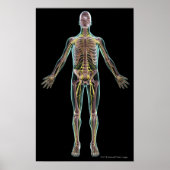

Poster Illustration of the nervous system

The nervous system Copyright: MedicalRF.com

The nervous system is an organ system containing a network of specialized cells called neurons that coordinate the actions of an animal and transmit signals between different parts of its body. In most animals the nervous system consists of two parts, central and peripheral. The central nervous system of vertebrates (such as humans) contains the brain , spinal cord , and retina . The peripheral nervous system consists of sensory neurons, clusters of neurons called ganglia , and nerves connecting them to each other and to the central nervous system. These regions are all interconnected by means of complex neural pathways. The enteric nervous system , a subsystem of the peripheral nervous system, has the capacity, even when severed from the rest of the nervous system through its primary connection by the vagus nerve , to function independently in controlling the gastrointestinal system.

Neurons send signals to other cells as electrochemical waves travelling along thin fibers called axons , which cause chemicals called neurotransmitters to be released at junctions called synapses . A cell that receives a synaptic signal may be excited, inhibited, or otherwise modulated. Sensory neurons are activated by physical stimuli impinging on them, and send signals that inform the central nervous system of the state of the body and the external environment. Motor neurons, situated either in the central nervous system or in peripheral ganglia, connect the nervous system to muscles or other effector organs . Central neurons, which in vertebrates greatly outnumber the other types, make all of their input and output connections with other neurons. The interactions of all these types of neurons form neural circuits that generate an organism's perception of the world and determine its behavior. Along with neurons, the nervous system contains other specialized cells called glial cells (or simply glia), which provide structural and metabolic support.

Nervous systems are found in most multicellular animals, but vary greatly in complexity. Sponges have no nervous system, although they have homologs of many genes that play crucial roles in nervous system function, and are capable of several whole-body responses, including a primitive form of locomotion. Placozoans and mesozoans —other simple animals that are not classified as part of the subkingdom Eumetazoa —also have no nervous system. In Radiata (radially symmetric animals such as jellyfish) the nervous system consists of a simple nerve net. Bilateria , which include the great majority of vertebrates and invertebrates, all have a nervous system containing a brain, one central cord (or two running in parallel ), and nerves. The size of the bilaterian nervous system ranges from a few hundred cells in the simplest worms, to on the order of 100 billion cells in humans. Neuroscience is the study of the nervous system.